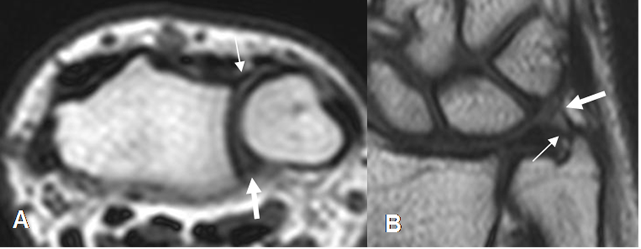

Fig 23. Complejo del FCT.

A: RM axial en T1. Ligamentos radioulnar anterior (Flecha delgada) y radioulnar posterior (Flecha gruesa).

B: RM coronal en T2. Ligamentos ulnosemilunar (Flecha delgada) y ulnopiramidal (Flecha gruesa).